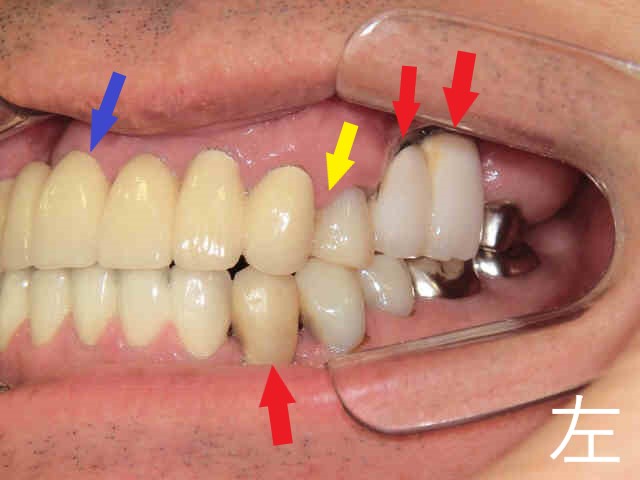

《下顎の状態》

同様に残根歯が複数確認され、保存が困難な部位が散見されました(黄色矢印部位)。

《奥歯の咬合状態》

左右の奥歯についても、上下で残根状態の歯が咬合しており、このままでは補綴物(被せ物や入れ歯)を入れることが困難な状況でした。